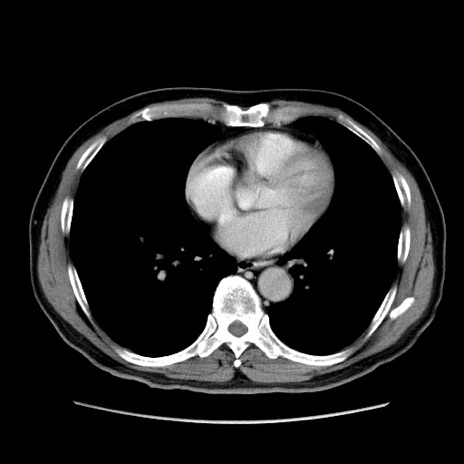

症例34(横断像)

【症例】60歳代 男性

【主訴】右鼠径部膨隆

【現病歴】1年程前より右鼠径部膨隆あり。自己にて還納可能だったため放置していた。3時間前より右鼠径部の脱出を認め、還納困難となり受診。

【身体所見】右鼠径部に小児頭大の膨隆あり。弾性硬であり、用手還納は困難。左鼠径部にも膨隆を認める。脱出はなし。